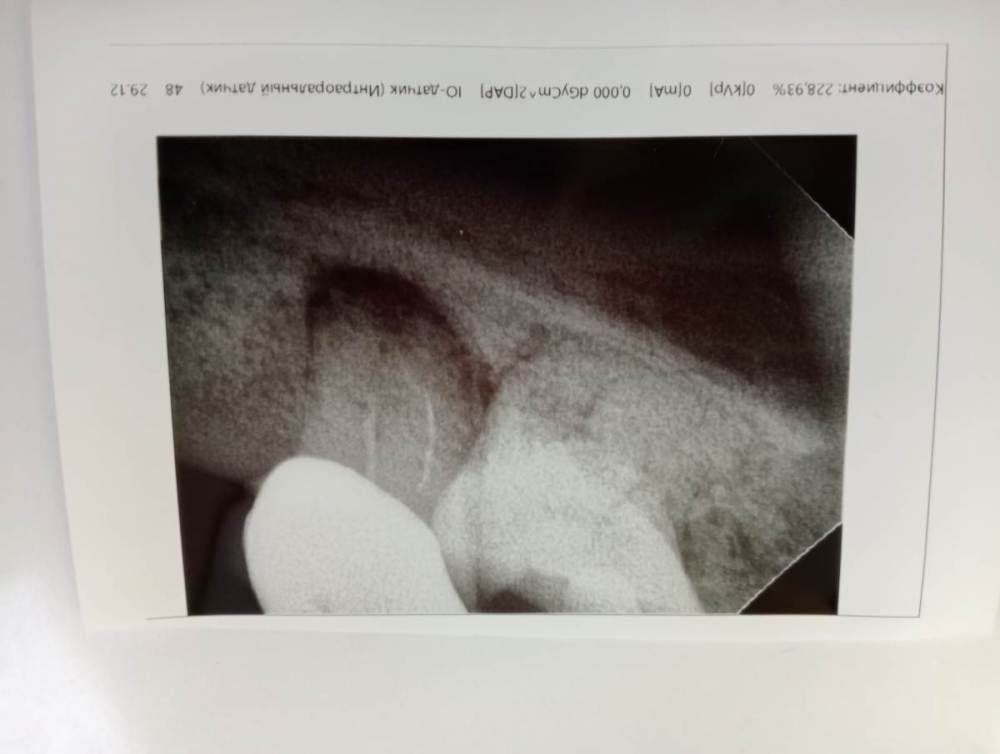

Маri 13 Опубликовано 23 января, 2023 Поделиться Опубликовано 23 января, 2023 Здравствуйте! Подскажите, удалять ли зуб ? Нижняя 7-ка под коронкой. Киста уже лет 7, не беспокоила и не росла. Два года назад перед установкой коронки перелечивали каналы, стала меньше, но до конца не прошла. Сейчас сказали, что воспаление ( это помимо кисты что-ли , или кисту и имели ввиду ? ) и надо удалять зуб. Зуб не болит, слегка пошатывается, но возможно из-за проблемных десен. Ссылка на комментарий

red_butler Опубликовано 24 января, 2023 Поделиться Опубликовано 24 января, 2023 26 минут назад, Маri 13 сказал: Так это все же киста на снимке или какое-то другое воспаление? это хронический апекальный периодонтит 27 минут назад, Маri 13 сказал: И можно ли убрать это воспаление хирургическим путем ( разрезав десну ) не снимая коронки и не перелечивая каналы? можно, но без перелечивания корневых каналов это малоэффективно Ссылка на комментарий